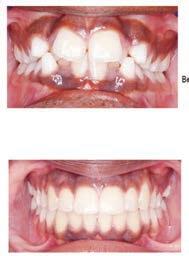

๊ฑด๊ฐํ ๋ฏธ์, ํดํผ์ค๋ง์ผ ์น๊ณผ์์

์์ํ์ธ์.

์ต์ ์ฅ๋น์ ์น์ ํ ์ง๋ฃ, ์ํ๋ํธ๊น์ง ๋ฏฟ๊ณ ๋งก๊ธฐ์ธ์!

๊ฐ์กฑ ๋ชจ๋์ ๋ฐ์ ๋ฏธ์๋ฅผ ์ง์ผ์ฃผ๋ ํดํผ

์ค๋ง์ผ ์น๊ณผ์์๋ ๊ฑด๊ฐ๋ณดํ๊ณผ ๋ฉ๋์ผ์ด,

๋ค์ํ PPO ๋ณดํ์ ์ทจ๊ธํ๋ฉฐ, ์์ฝ๋ถํฐ

์ง๋ฃ๊น์ง ๋ชจ๋ ๊ณผ์ ์์ ํ์์ ํธ์์

๋ง์กฑ์ ์ต์ฐ์ ์ผ๋ก ํ๋ค.

ํนํ ํดํผ์ค๋ง์ผ ์น๊ณผ๋ ์ํ๋ํธ ์น๋ฃ

์ ๊ฐํ ์์ ๊ฐ์ ๊ฐ์ง๊ณ ์๋๋ฐ, ์์์

์น์ ๋ ์ฌ์ฉํ๋ ํ, ์ฆ ์น์์ ํฑ ๊ทผ์ก

์ ์ฌ์ฉํ์ฌ ์์์ ์๊ฒ ๋ถ์๋ ๋ฅ๋ ฅ๊ณผ

์ฌ๋ฏธ์ฑ์ ๋์์ ๋ง์กฑ์ํค๋ ์ํ๋ํธ๋

์์ฐ ์น์์ ๊ฐ์ฅ ๊ฐ๊น์ด ๋์ฒด ์น๋ฃ๋ก, ํ

๋์ ๋นํด ๋ ๋จ๋จํ๊ณ ์ค๋ ์ฌ์ฉํ ์ ์

์ธ์ ์น์๋ฅผ ๊น์ ํ์๊ฐ ์์ด ๊ตฌ๊ฐ ๊ฑด๊ฐ์ ์ ์งํ๋ ๋ฐ๋ ๋์์ด ๋๋ค. ํดํผ์ค๋ง์ผ ์น๊ณผ๋ ๋ณต์กํ ๊ตฌ๊ฐ์ธ๊ณผ ์์ ๊ณผ ์ง๋จ์ ์ํด ์น๊ณผ์ ์ฉ 3D CT ์ค์บ๋๋ฅผ ๊ฐ์ถ๊ณ ์์ผ๋ฉฐ, ์ด๋ฅผ ํตํด ์ ํํ๊ณ ์์ ํ ์ํ๋

ํธ ์์ ์ด ๊ฐ๋ฅํ๋ค. ํฑ๋ผ ์ํ, ์ ๊ฒฝ ์์น, ๋ผ์ ๋ฐ๋๊น์ง ์ ๋ฐํ๊ฒ ๋ถ

์ํ์ฌ ํ์ ๊ฐ๊ฐ์ธ์๊ฒ ์ต์ ํ๋ ์น๋ฃ ๊ณํ์ ์๋ฆฝํด๋๋ฆฐ๋ค.

๋ฟ๋ง ์๋๋ผ, ์ฌ๋ฏธ๋ณด์ฒ ๊ณผ ๋ฏธ์ฉ์น๋ฃ, ์ผ๋ฐ์น๊ณผ, ์์์น๊ณผ, ๊ตฌ๊ฐ์ธ๊ณผ, ์ ๊ฒฝ

์น๊ณผ ๋ฑ ๋ค์ํ ๋ถ์ผ์ ์ ๋ฌธ ์๋ฃ์ง์ด ํจ๊ปํด ํ ํ ์น๊ณผ ์ง๋ฃ๋ฅผ ์์คํฑ ์ผ๋ก ์ ๊ณตํ๊ณ ์๋ค.

ํดํผ์ค๋ง์ผ ์น๊ณผ์์๋ ์ ํธ๋(Aetna), ์ค์ฌ(Anthem), ํด๋ ๋ฒ์ผ์ด (Clever Care), ์์คํฐ๋ฐ(Astiva), ํด๋จธ๋(Humana), ๋ฆฌ๋ฒํฐ(Liberty), ์ ๋ ์ดํฐ๋ํฌ์ค์ผ์ด(United Healthcare) ๋ฑ. ๋ค์ํ ๋ณดํ์ ์ทจ๊ธํ๊ณ ์๊ณ , ๋ฉ๋์นผ/๋ฉ๋์ผ์ด PPO ๋ณดํ ํ์ํ๋ค.

์ข์ ์ฌ๋ฃ์ ๊ณ ํ์ง ์ง๋ฃ, ์ต์ ๊ธฐ์ , ๊ทธ๋ฆฌ๊ณ ํ์๋ฅผ ์๊ฐํ๋ ์ง์ฌ์ด ์๋ ํดํผ์ค๋ง์ผ ์น๊ณผ์์ ์จ ๊ฐ์กฑ์ ๊ฑด๊ฐํ ๋ฏธ์๋ฅผ ๋์ฐพ์๋ณด์.

๋ฌธ์ ๋ฐ ์์ฝ: 818-775-1200